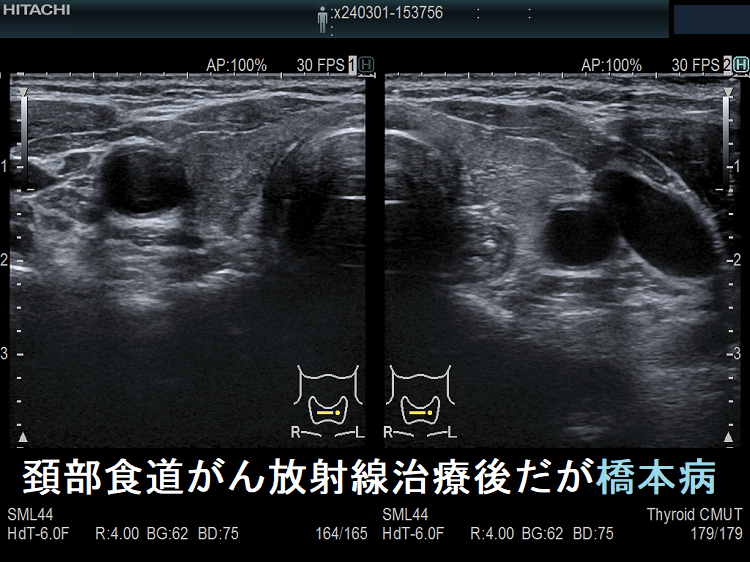

頚部食道がん放射線治療後だが橋本病